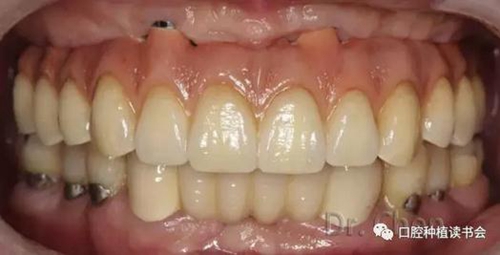

患者佩戴義齒后的口內(nèi)像和口外像(圖11、12),義齒外形、顏色、發(fā)音滿意,

曲斷片顯示所有氧化鋯接口與Multi-unit基臺之間完全就位,骨水平穩(wěn)定于植體頸部(圖13)。

患者佩戴永久修復體后半年復診,咀嚼功能及美觀、發(fā)音均滿意。骨水平穩(wěn)定,無機械及生物學并發(fā)癥。

▲口內(nèi)連接全氧化鋯一體橋后

▲上頜佩戴固定橋后的微笑像